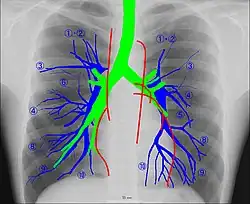

Radioanatomy (x-ray anatomy) is an anatomy discipline that involves studying anatomy through the use of radiographic films.[3] The x-ray film represents a two-dimensional image of a three-dimensional object due to the summary projection of different anatomical structures onto a planar surface.

It requires certain skills for the correct interpretation of such images. Radiological anatomy is a necessary component of training for medical students and radiologists.